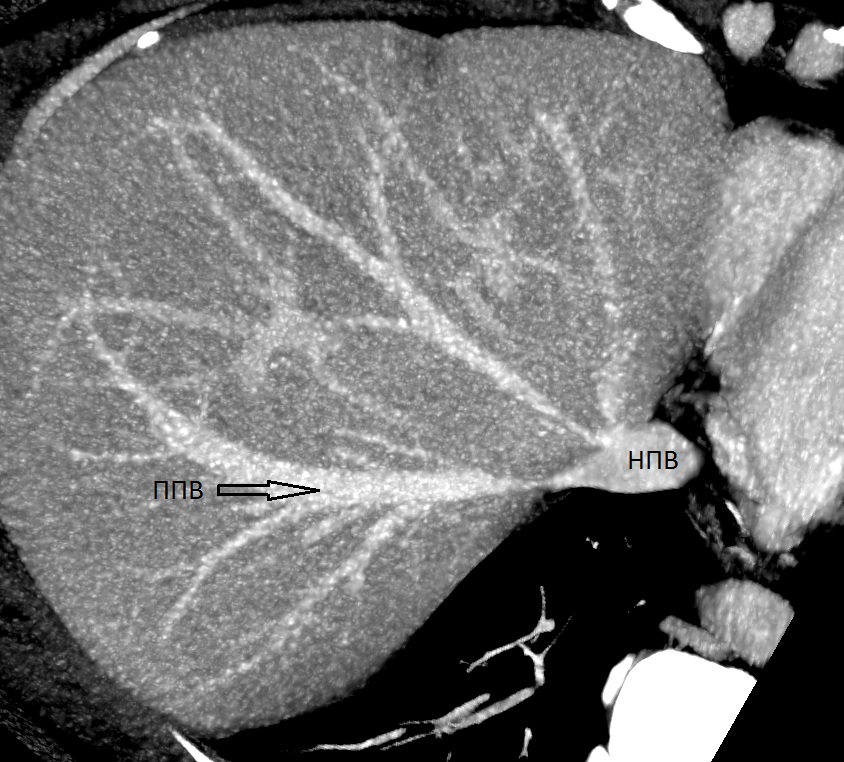

Результаты. Выявлено 14 подтипов анатомии эфферентных сосудов. Их классифицировали в 3 типа в зависимости от вклада срединной вены в отток крови от правой доли печени: кавальный (67,3%), кава-срединный (полусепаратный, 29%) и сепаратный (3,6%).

23. Тип H (снимок КТ). | |

| Тема | ||

| Тип | Исследовательские инструменты | |

Посмотреть

(93KB)

|

Метаданные ▾ | |